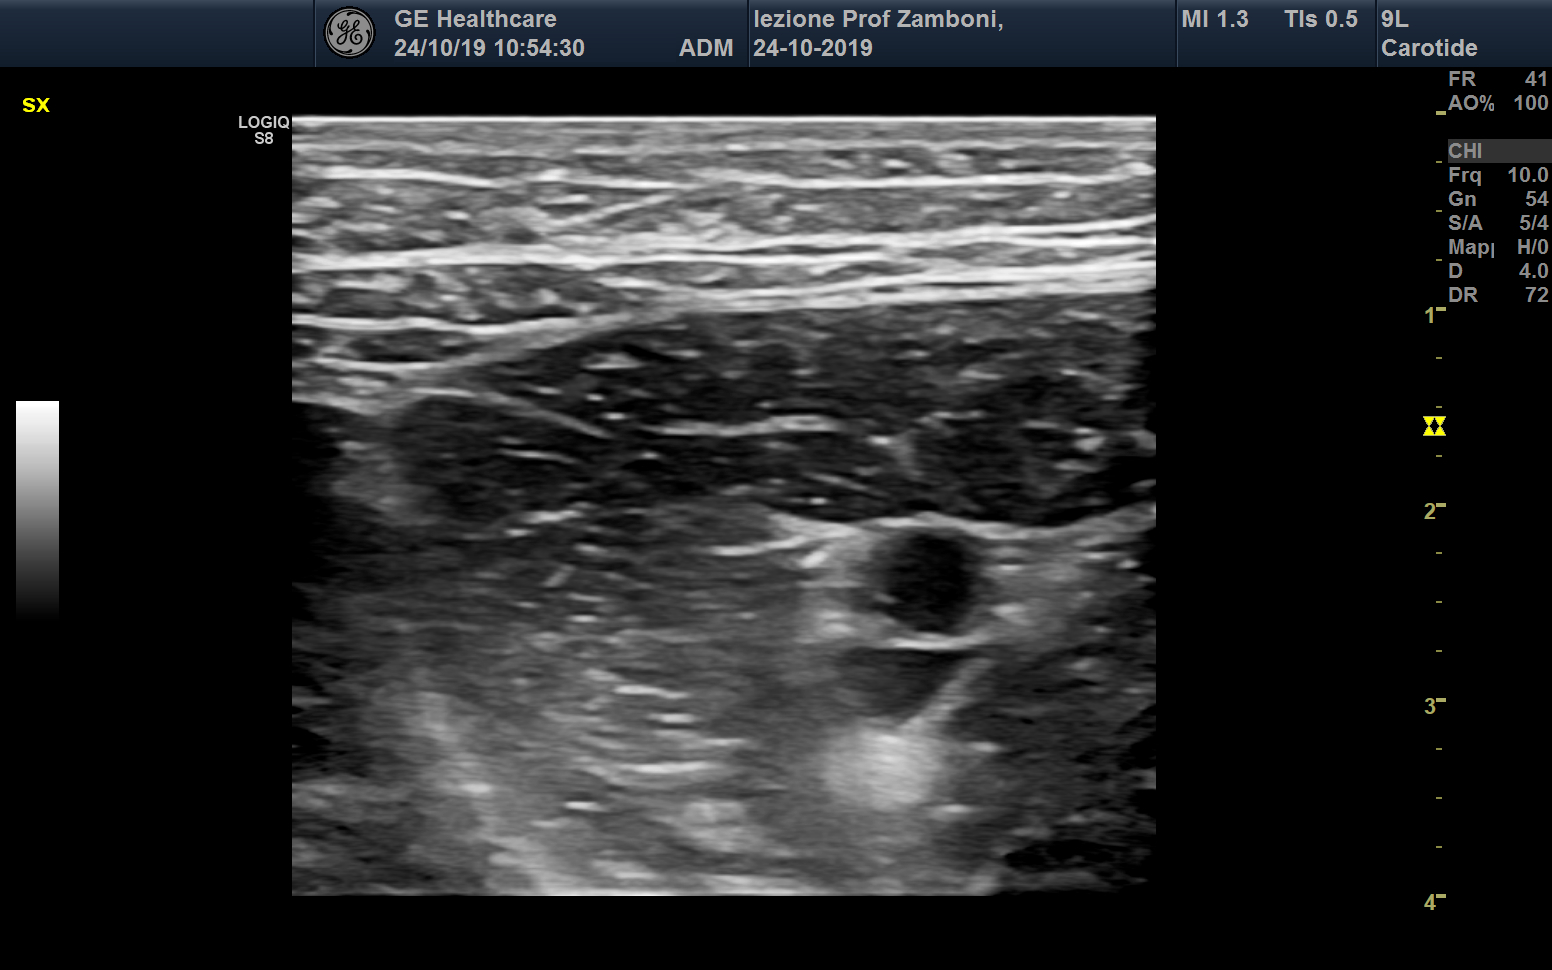

B mode Arteria e Vena femorale

JPEG image icon B mode Arteria e Vena femorale.jpg — JPEG image, 444 kB (455224 bytes)